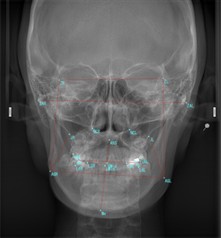

セファログラムには、「側面セファログラム」と「正面セファログラム」の2種類があります。

| 正面セファログラム | 顔の左右対称性、顎の幅、上下顎の横方向のバランス |

セファログラムでは、X線写真に基準点を設定し、角度や距離を測定することで骨格や歯の位置関係を数値化します。

これにより、正確な診断や矯正治療の計画を立てるための重要な情報を得ることができます。

正面セファログラム